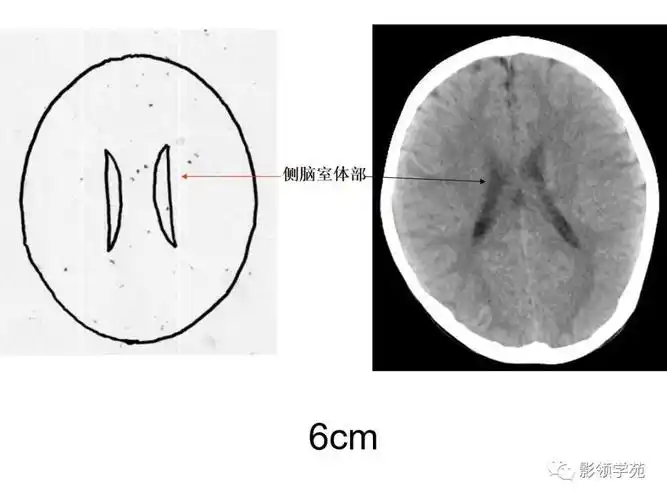

颅脑ct的正常解剖